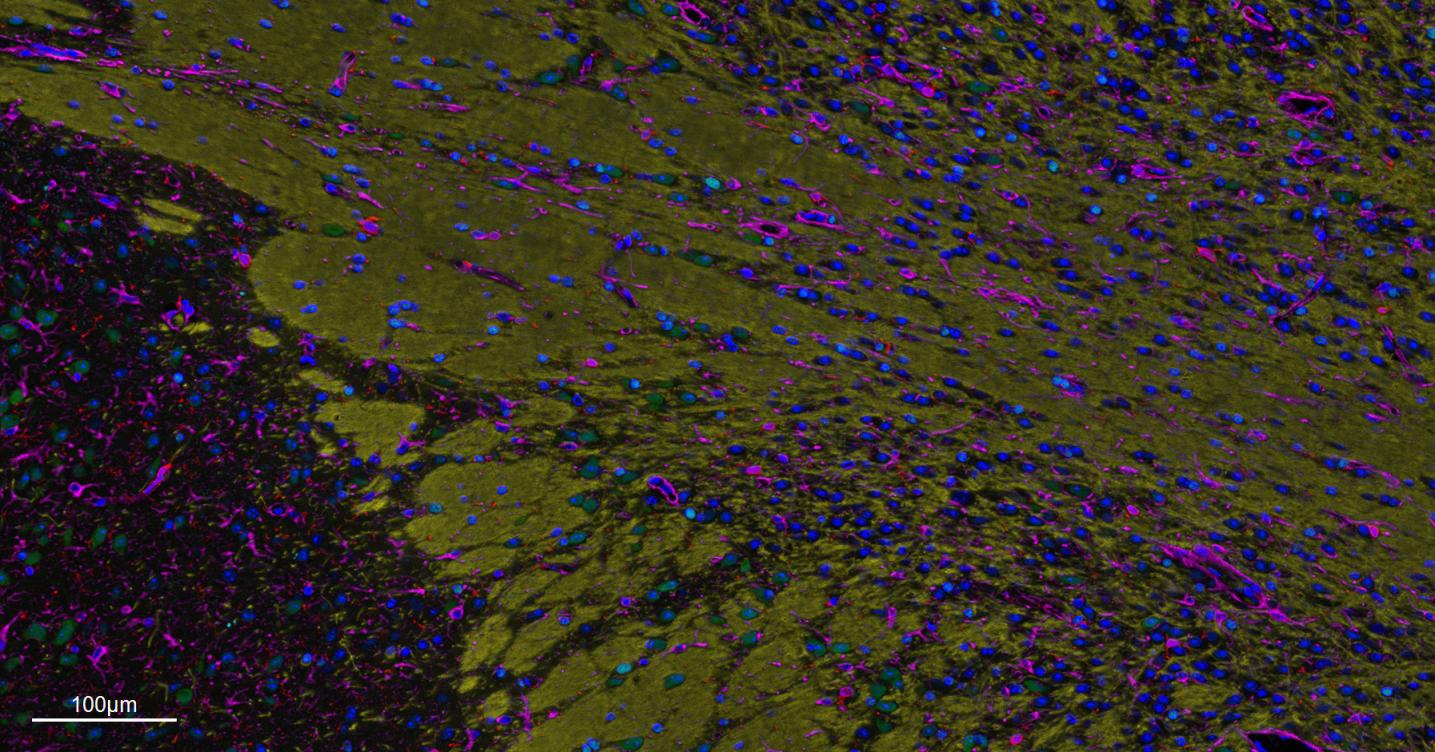

| IF | Human, Mouse, Rat | 1:200-1000 |